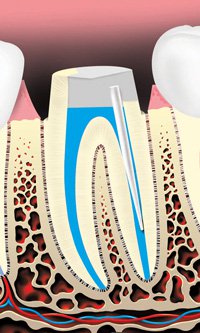

Diagram of a Healthy Tooth

The pulp is soft tissue inside the tooth that contains blood vessels and nerves. When the pulp becomes inflamed or infected, treatment is needed. The most common causes of pulp inflammation or infection are a cracked or chipped tooth, a deep cavity or filling, or other serious injury to the tooth. All of these can allow bacteria to enter the pulp.